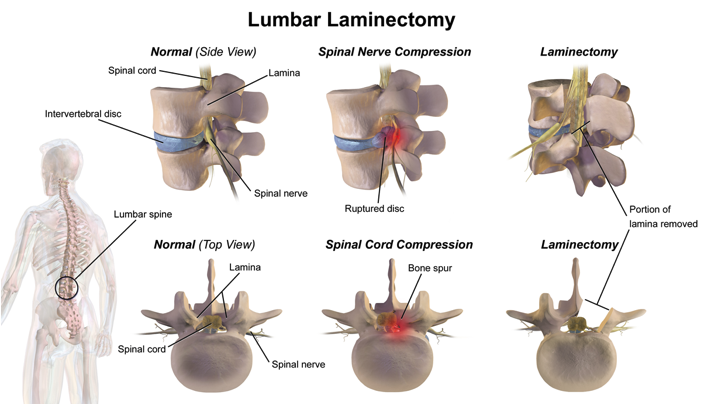

3. Lumbar laminectomy

The lamina is a component of the arch on the lumbar vertebra. Cased within the lamina is a circular space that hosts the spinal cord. In conditions such as spinal stenosis, the spinal cord can be compressed against structures such as ligaments or bones (image x). To remove this compression, a laminectomy is performed whereby the surgeon removes the lamina (image 7).

Image 7. A visual illustration of a lumbar laminectomy. Source.